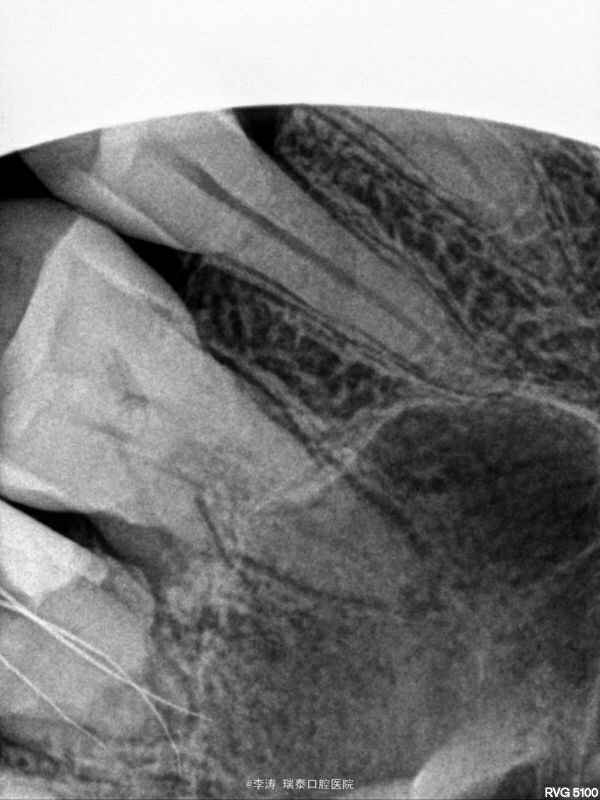

27牙伸长,松-,冷++,叩+-,近中邻面大面积龋坏,探及穿髓孔,x线片近中大面积龋坏近髓腔

27牙牙髓炎,行根管治疗 27磨短,测根长腭根11mm,近颊及远颊根15mm。置橡皮障,根管预备,根管消毒,根管充填。

1,关于伸长牙的修复问题,因为牙根比较短小,修复起来远期效果怎么样?伸长多少的牙齿需要拔掉呢?是没松动都可以修复吗? 2,后牙上橡皮障以后很难拍片子,所以本病例拍片的时候全是取下来的。不知道大家是怎么做的呢?